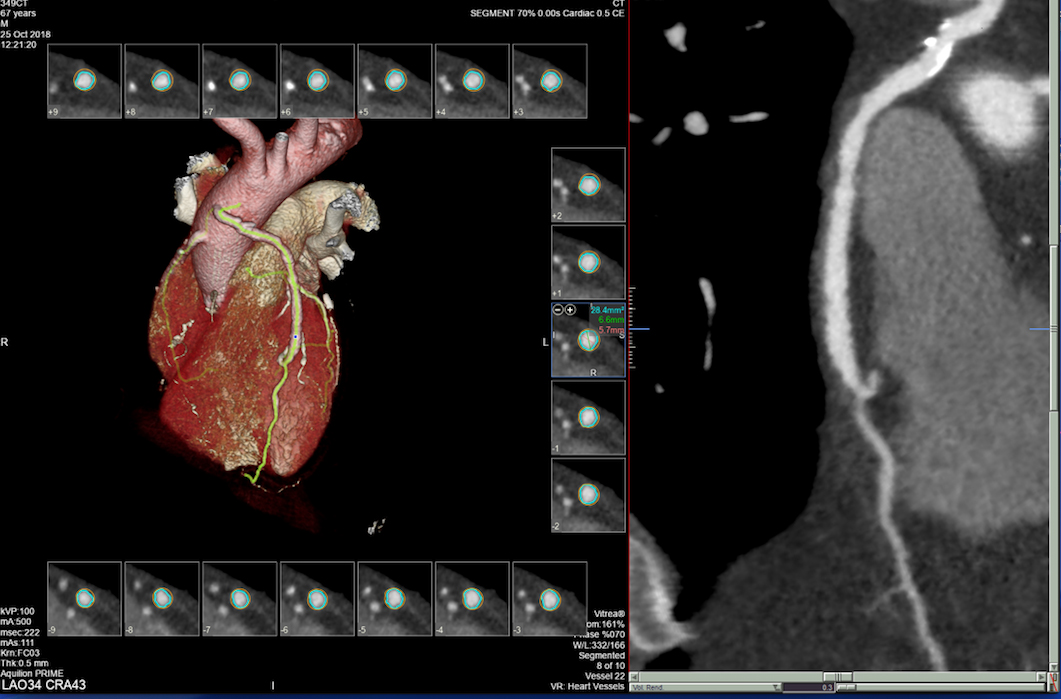

Također u slučaju pojave boli u prsima, gdje nema EKG promjena i lab.nalazi su uredni, radi se takozvani «triple rule-out» CT koronarografija-da bi se jednim pregledom isključila bolest koronarnih arterija, plućna tromboembolija ili disekcija aneurizme aorte, od kojih je svaka ponaosob potencijalno fatalna.

• MSCT koronarografija (prikaz krvnih žila srca CT-om, bez neugodnosti i komplikacija koje nosi klasična koronarografija), u saradnji s Poliklinkom dr.Al-Tawil